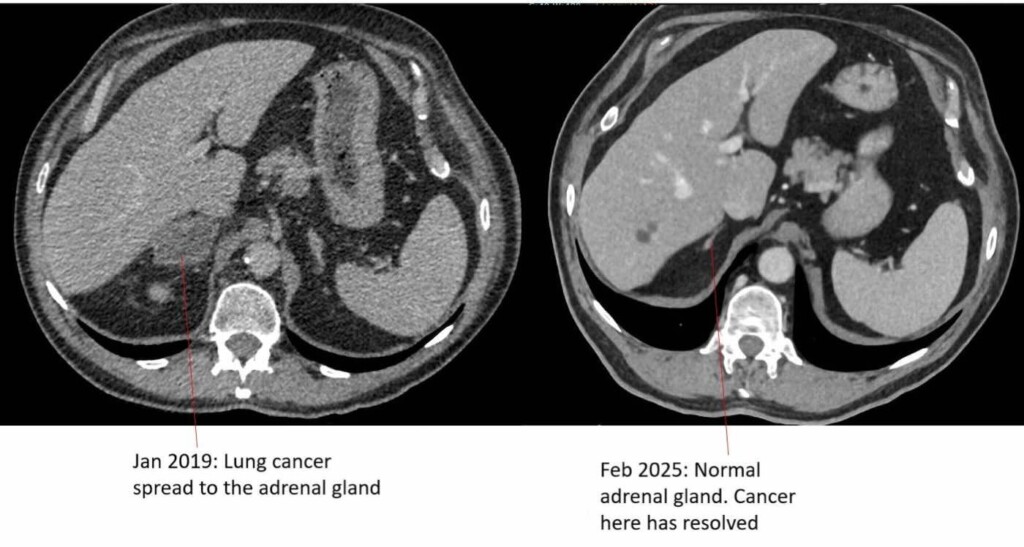

A grandad diagnosed with advanced lung cancer which often leaves patients dead within four months has become free of the disease after being treated with a new immunotherapy drug.

After receiving the treatment for around two years, Jeff was told that he is officially cancer free.

Dr Woolf says he’s “delighted” that Jeff has had such a positive response to the treatment and is now cancer-free six years after his diagnosis.

“Stage four lung cancer remains very serious with average survival figures of less than a year. However, new treatments such as immunotherapy are a game changer for some of our patients.